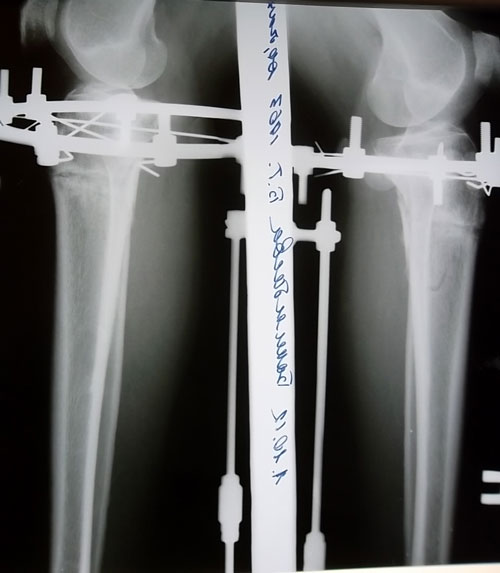

рентгеновские снимки в день снятия аппаратов Илизарова - Онипко.Вот такая МОЩНАЯ костная мозоль бывает у женщин в 49 лет через 3 месяца после операции. (в день снятия аппаратов)

Пациентка Надежда.

Дата операции 26.06.2012г.

Дата снятия 01.10.2012г.

Срок лечения 95 дней.